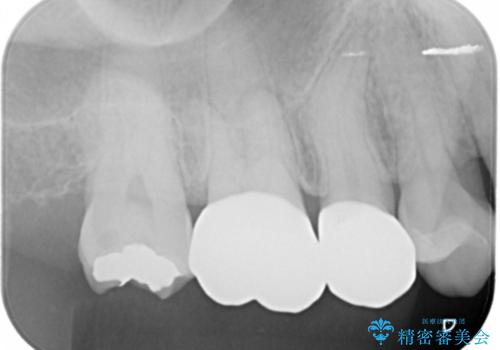

- 右上7番の銀歯のやりかえを主訴に来院された患者様です。

切削量・形態を考慮し、セラミックインレーでの治療を計画しました。